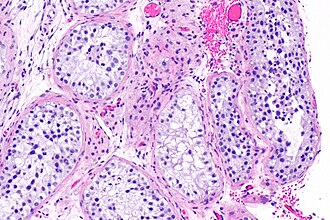

Mixed pattern male infertility (Sertoli cells only mixed with hypospermatogensis). H&E stain. | |

Male infertility on testicular biopsy shows one the following patterns:[1]

- Normal testis.

- Hypospermatogensis.

- Maturation arrest.

- Sertoli cells only.

- Seminiferous tubule hyalinization

- Some combination of the above patterns.

Mixed pattern

LEFT TESTIS, BIOPSY WITH SPERM RETRIEVAL: - SERTOLI CELLS ONLY REGIONS (25% OF BIOPSY) INTERMIXED WITH HISTOLOGICALLY NORMAL TESTIS (75% OF BIOPSY) WITH NORMAL NUMBERS OF SPERM. - NEGATIVE FOR SIGNIFICANT SEMINIFEROUS TUBULE HYALINIZATION. - NEGATIVE FOR SIGNIFICANT INFLAMMATION. - NEGATIVE FOR GERM CELL NEOPLASIA IN SITU (INTRATUBULAR GERM CELL NEOPLASIA).